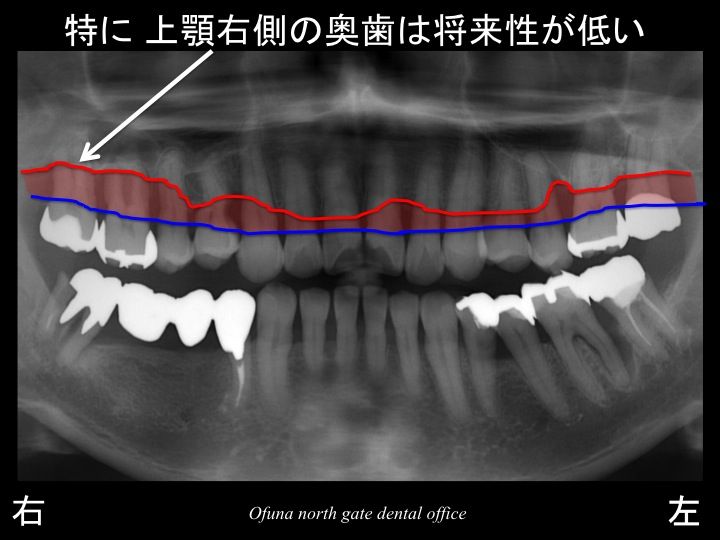

まず骨吸収の状態です。

いつものように 骨吸収の状態を分かりやすくするために

骨吸収の状態を線で書いたのが以下のレントゲンになります。

青線が骨吸収を起こす前の骨の位置です。

赤線は、現在の骨の位置です。

かなりの骨吸収が起こっているのが分かるかと思います。

さらに わかりやすくするために、

骨吸収部位を赤色で表示します。

ここで注目したいのが奥歯です。

奥歯は骨吸収が非常に大きいのです。

奥歯は将来性が低いと言えます。

このことを考えて治療計画を立てることが重要です。

特に上顎右側の奥歯は骨吸収が非常に大きいのです。

この歯は最も将来性が低いと言えます。